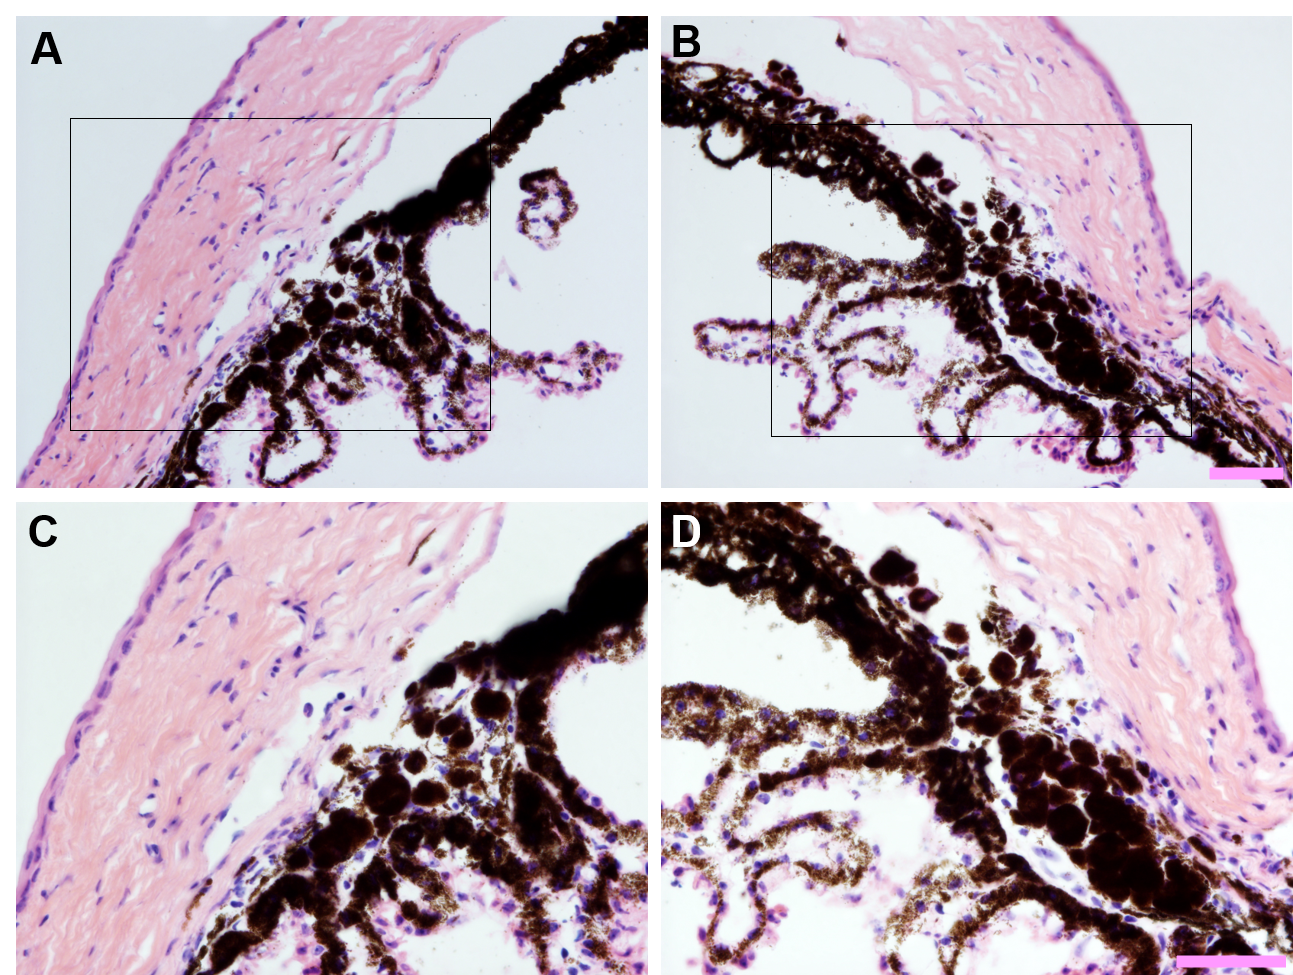

To access the data, click or select the words “Appendix 9.” Persistence of clump cells in the iridocorneal angle of eyes following intraocular Ad5 injection. Light micrographs collected from opposite poles (left vs. right column) of hematoxylin and eosin-stained histological sections from the same eye shown at (A–B) 200X and (C–D) 400X total magnification. Areas within inset boxes (top row) are show at higher magnification below (bottom row). Note that despite some variability, there is a persistent localization of clump cells deep within the iridocorneal angle with proximity to the drainage structures. Scale bar = 50 µm.